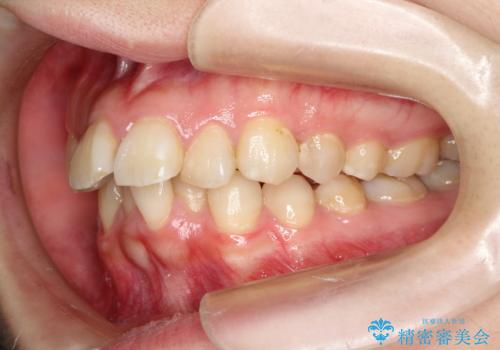

- 口元の閉じにくさと、前歯のでこぼこの歯並びを気にして来院された患者様です。

口元を積極的に引っ込めるために、上下左右の小臼歯計4本を抜歯することとしました。

咬み合わせが深く、咬合力強いため、補助装置を使用しながら積極的に口元を下げることとしました。